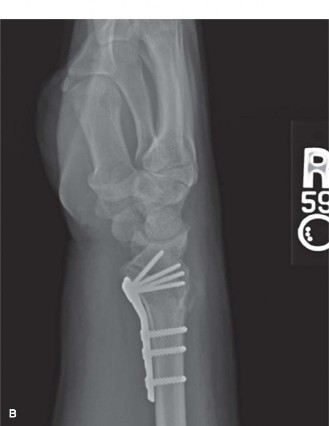

Clinical & Radiographic Imaging

Fixation Construct (Volar Locking Plate):

1.

Plate Selection and Positioning:

An anatomically contoured, variable-angle volar locking plate (e.g., from the Stryker VariAx 2, DePuy Synthes DVR, or Acumed Acu-Loc systems) was selected. The plate was provisionally positioned on the volar aspect of the distal radius. The proximal edge of the plate was positioned just proximal to the watershed line to avoid potential impingement on the flexor pollicis longus (FPL) tendon while still allowing for adequate screw length in the distal fragment.

Distal Fixation:

Under fluoroscopic control, variable-angle locking screws were inserted into the distal fragments, targeting the subchondral bone for maximum stability. Screw trajectory was carefully planned to avoid penetrating the joint surface or impinging on the DRUJ.

Restoration of normal volar tilt (10-15 degrees), absence of articular step-off, and appropriate screw lengths (all screws subchondral but not penetrating joint). The critical volar tilt was confirmed at +12 degrees.